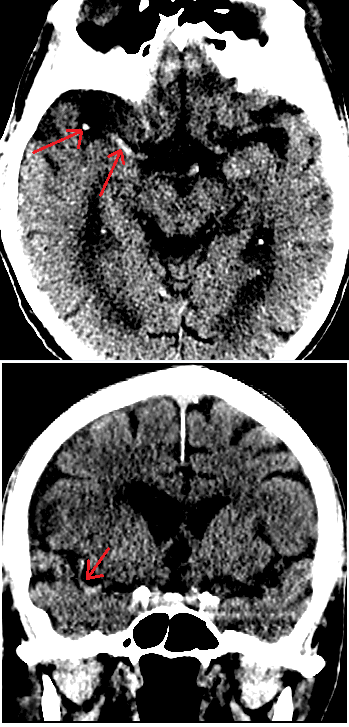

• “Dense MCA sign” is caused by opacification of the MCA by a thrombus. When noted this is likely to be in the horizontal body of the MCA coming off of the Circle of Willis, but more subtly can also be sometimes seen in a branch of the MCA. In the figure below the right MCA is dense and both an MCA “dot sign” as the MCA enters the Sylvian fissure and a linear section of MCA coming off the Circle of Willis and running along the skull base are visible in the axial cut. In the coronal section a long curved portion of the MCA is clearly visible.

Dense MCA sign in R hemisphere